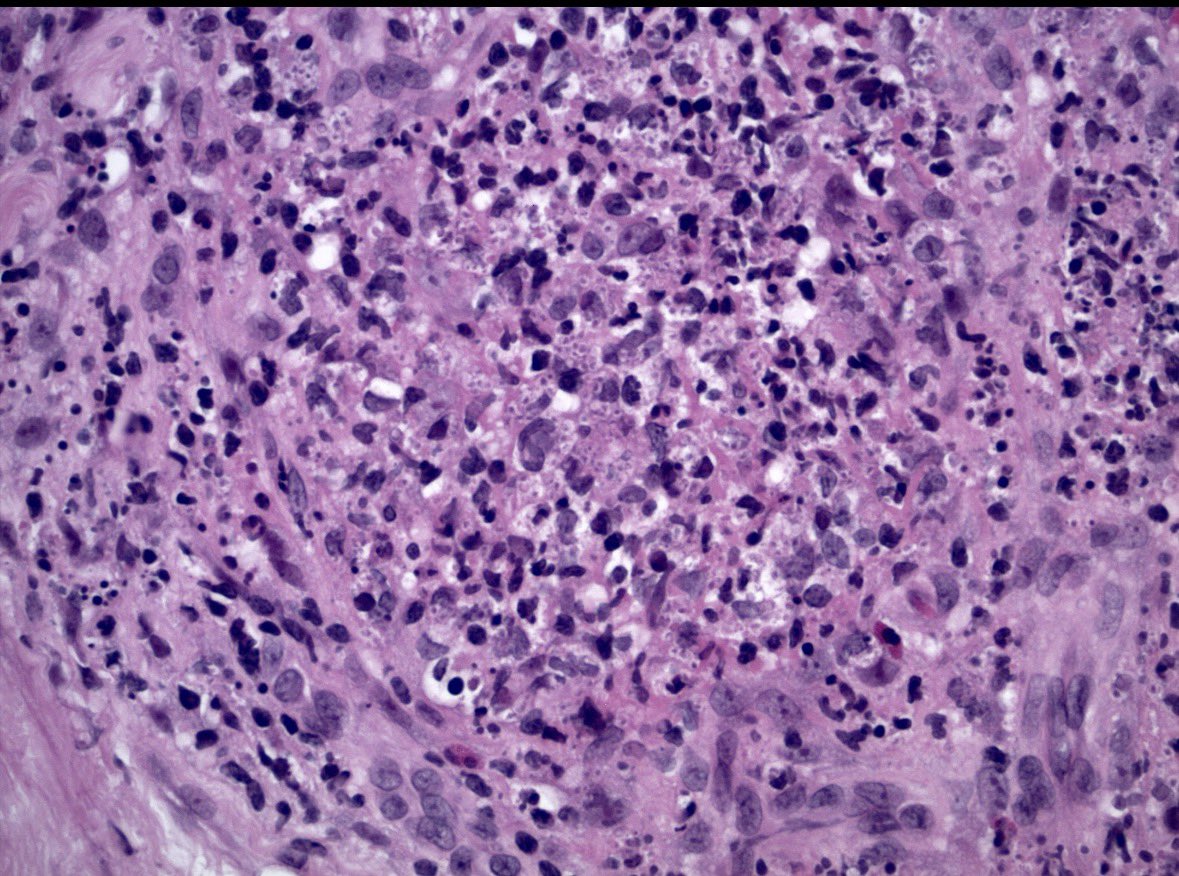

Diagnosing granulomatosis with polyangiitis on small biopsies (especially if not considering it) is very challenging. ANCA serologies, negative cultures, and pathologic suspicion were crucial in this case. Not everything is cancer at a cancer center. #lungpath #pathology #moffitt